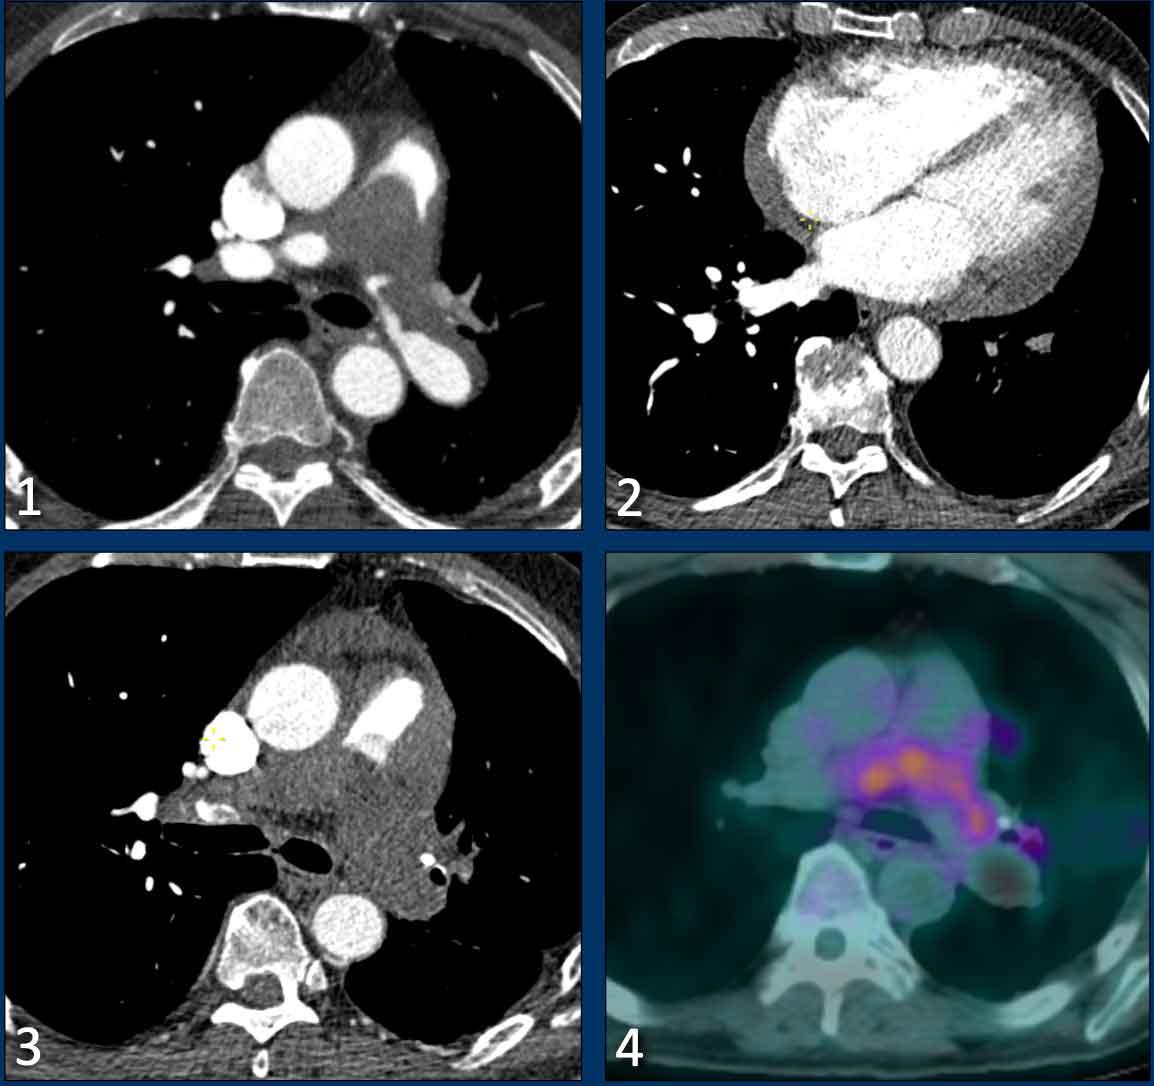

Sarcôm động mạch phổi

Chẩn đoán phân biệt quan trọng nhất với bệnh huyết khối tắc mạch mạn tính là sarcôm động mạch phổi, một khối u ác tính nguyên phát hiếm gặp xuất phát từ thành mạch.

Bệnh thường biểu hiện là khuyết thuốc cản quang trung tâm trong lòng động mạch phổi và ban đầu có thể bị nhầm lẫn với huyết khối.

Mặc dù có thể có các dấu hiệu tắc nghẽn lưu lượng máu và căng thẳng tim phải, phì đại thất phải thường vắng mặt do khối u tiến triển nhanh.

Các đặc điểm hình ảnh gợi ý sarcôm động mạch phổi bao gồm:

- Khối nội mạch dạng giãn rộng, có thể có thành phần xâm lấn ngoài mạch.

- Xâm lấn van động mạch phổi và/hoặc đường ra thất phải.

- Vắng mặt các dấu hiệu phụ của bệnh huyết khối tắc mạch mạn tính.

- Ngấm thuốc tương phản sau khi tiêm thuốc cản quang.

- Tăng hấp thu FDG trên PET (thường gặp, nhưng có thể thấp hoặc không có).

- Tăng kích thước mặc dù đang điều trị chống đông.

Hình ảnh

- Có khuyết thuốc cản quang lớn trong lòng các động mạch phổi trung tâm.

- Đáng chú ý, không có phì đại hay giãn thất phải rõ ràng.

- Tăng kích thước tiến triển mặc dù đang điều trị chống đông.

- Hoạt tính chuyển hóa trên hình ảnh FDG-PET.